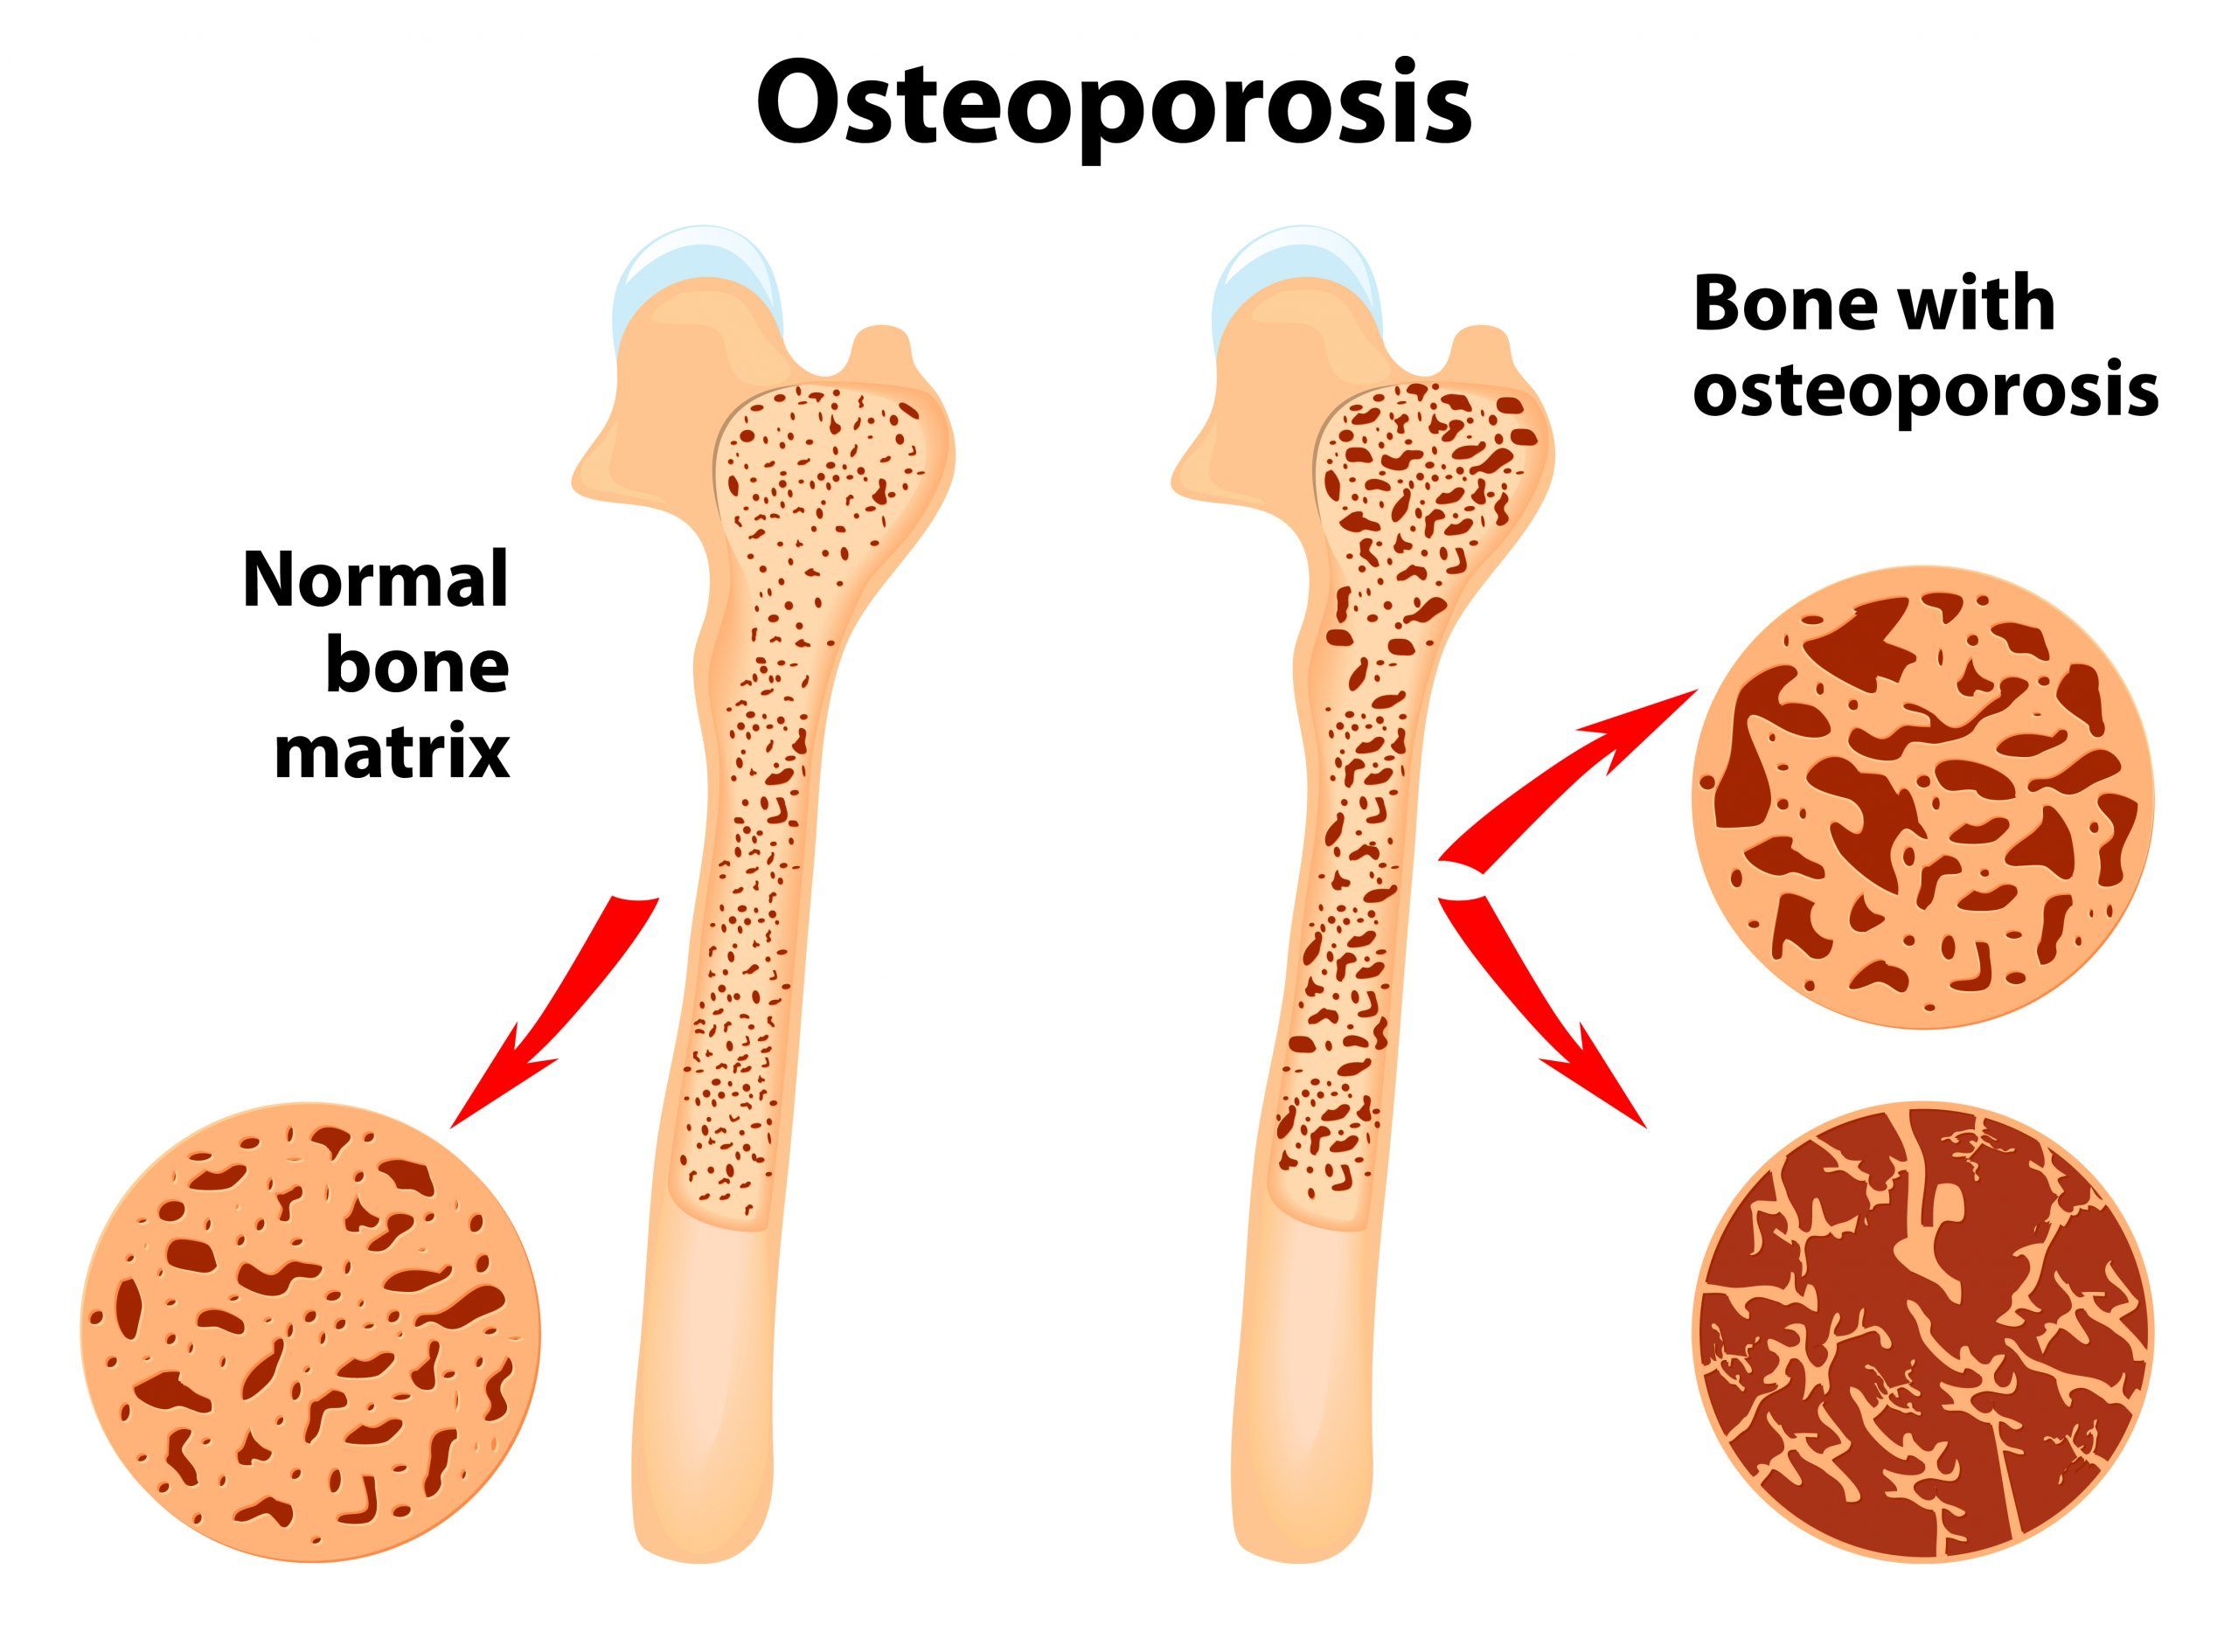

Alimentul care previne depunerea colesterolului pe vasele de sânge și combate osteoporoza

Soia (Glycine max) aparține familiei leguminoaselor pentru boabe, din care mai fac parte fasolea, mazărea, lintea. Soia conține până la 40% protide (comparativ cu carnea,… Citește mai mult »Alimentul care previne depunerea colesterolului pe vasele de sânge și combate osteoporoza